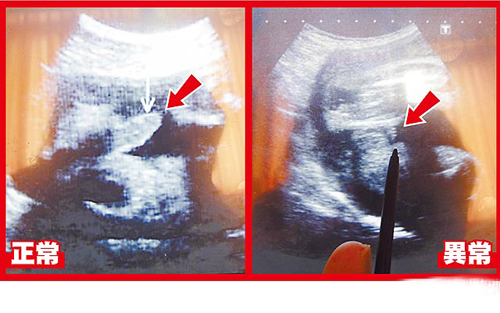

超聲波可看到胎兒生殖器,左圖箭頭處為28周正常男嬰生殖器:右圖箭頭處為異常男嬰28周時生殖器畫面。圖片來源:臺灣媒體

據(jù)報道,臺中大里仁愛醫(yī)院婦產(chǎn)科醫(yī)師李瑞祺說,這名30歲產(chǎn)婦在懷孕28周時出現(xiàn)密集陣痛,醫(yī)院緊急幫她安胎、進行超聲波等檢查,赫然發(fā)現(xiàn)胎兒生殖器特別短,陰囊還是空的,懷疑染色體或基因異常導(dǎo)致生殖器過短與隱睪癥。但孕婦在26周時曾進行羊膜穿刺檢查,顯示性染色體正常。